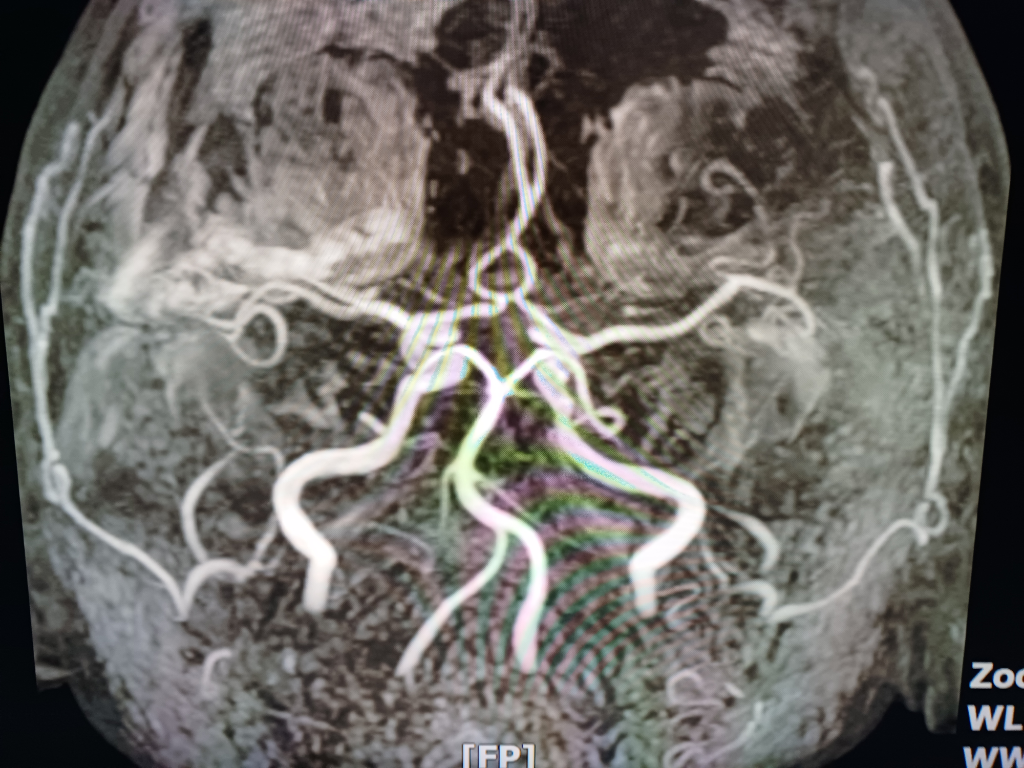

뇌 mri mra를 찍었는데 전문가분들의 고견을 구합니다.

안녕하세요.불편한 어지러움이 한달이상 지속되어 혹뇌쪽 이상이 아닌가 싶어 오늘급하게 mri mra를 촬영하고 왔습니다.결과를 바로 확인할수 있는줄 알았으나 일주일정도 기다려야 판독이 나온다하여 급한 마음에 사진 몇장 첨부하오니 답변해주시면 감사하겠습니다!!

• 3번 째 사진

업로드해주신 MRI 및 MRA 영상은 특별히 이상한 소견이 보이지 않습니다

뇌실질에 이상소견 없으며 뇌혈관이 막여있거나 좁아진 부분도 보이지 않습니다

현재 올려주신 사진만으로는 아주 큰 병변 이 있어 보이지는 않으나, MRI의 경우 연속된 단면을 모두 봐야 병변을 정확히 확인할 수 있으므로 해당 사진들만으로는 병변의 유무를 모두 다 확인 불가능합니다. 추후 판독을 기다려 보시기 바랍니다.